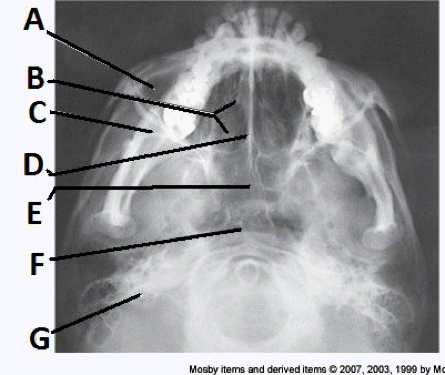

____ 10. Examine the image of the paranasal sinuses below. The letter D labels the:

a. crista galli

b. vomer

c. cribriform plate

d. perpendicular plate of the ethmoid bone

bb. vomer

____ 37. Examine the image of the paranasal sinuses below. The letter F labels the:

a. maxillary sinuses

b. sphenoid sinuses

c. ethmoid sinuses

d. pharynx

dd. pharynx

____ 174. Examine the image of the paranasal sinuses below. The letter E labels the:

a. sphenoid sinuses

b. ethmoid sinuses

c. frontal sinuses

d. maxillary sinuses

aa. sphenoid sinuses

(3) the central ray must be perpendicular to the infraorbitomeatal line and horizontal

a. 2 and 3

b. 1 and 2

c. 1 and 3

d. 1, 2, and 3

aa. 2 and 3